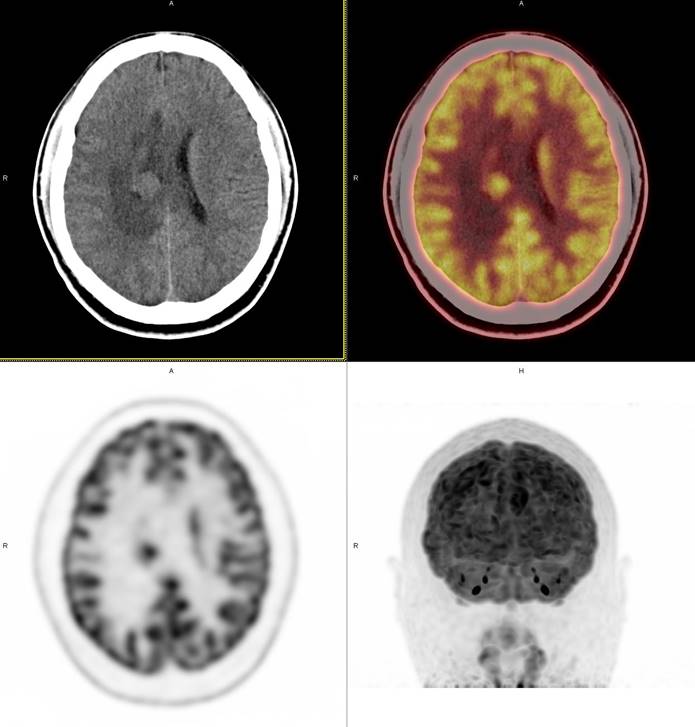

PET/CT影像圖

圖1

圖2

圖3

圖4

PET/CT檢查

影像診斷: 右側(cè)側(cè)腦室旁腦實(shí)質(zhì)內(nèi)結(jié)節(jié),代謝異常增高(SUVmax 12.13),伴瘤周水腫。

病理診斷:腦膜瘤二級(jí)